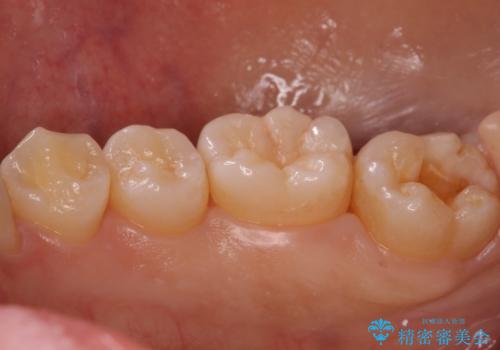

奥歯の深い黒ずみ セラミックインレーでの治療

- 奥歯の溝の黒ずみが気になるとのことで来院されました。

変色しない材料をご希望されたためセラミックインレーでの治療となりました。